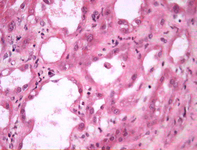

Necrose tubular aguda

Membranas basais desnudadas e presença de células no lúmen tubular

Cortesia da Puigvert Foundation, Barcelona, Espanha